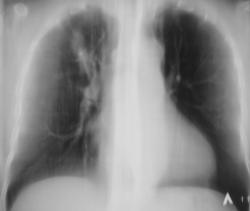

Иллюстрации 1, 2. Произведена рентгенография органов грудной полости в прямой стандартной и правой боковой проекциях. Справа на уровне 1 межреберья дифференцируется крупноочаговая тень овальной формы, от которой в сторону костальной плевры прослеживается линейный тяж. Справа регистрируется усиление и обогащение легочного рисунка. Рисунок правого корня усилен, обогащен, тень его несколько расширена.